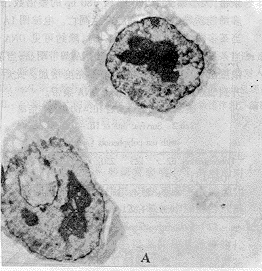

(三)茶多酚诱导HL-60细胞凋亡的细胞形态变化:图2A为未经药物作用的HL-60细胞透射电镜观察结果。图2B则为经250μg*mL-1茶多酚作用5 h后HL-60细胞透射电镜观察的结果,HL-60细胞染色体凝集裂解成碎片后整个细胞碎裂成由膜包绕的不连续的凋亡小体。

Fig 2 Changes in the morphology of HL-60 cells untreated and treated with TP.A:×3500,HL-60 cells untreated with TP. B:×5000, 250 mg/L TP treatment on HL-60 cells for 24 h displayed as apoptotic vehicles.

图2 对照组和茶多酚组HL-60细胞超微形态变化